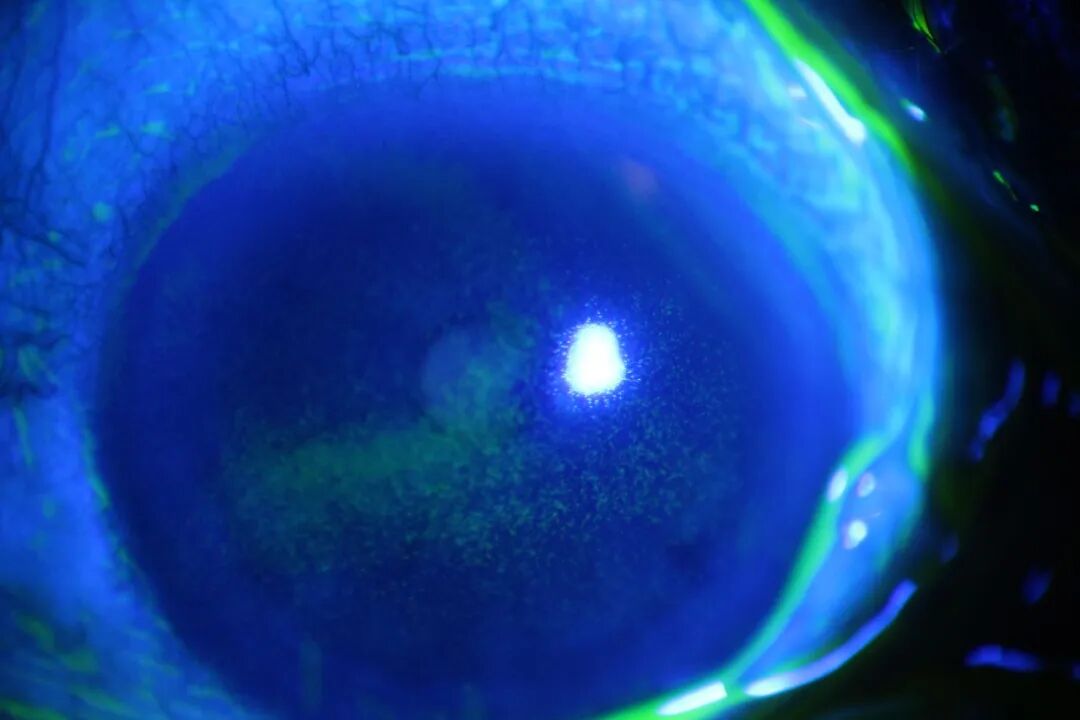

角膜炎

由于外源或内源致病因素引起的炎症反应,典型特征为睫状充血、角膜浸润及角膜溃疡形成。溃疡面愈合后,根据溃疡深浅程度不同,会遗留厚薄不等的瘢痕。